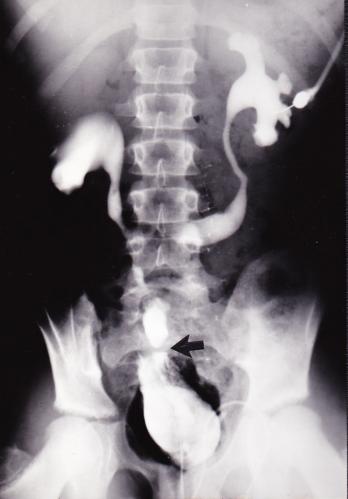

6½-Year-Old Female Patient Referred for Extensive Secondary Surgery of Her Cloacal Malformation (Hendren Patient Case) 6½-year-old female patient was referred in 1976 for extensive secondary surgery of her cloacal malformation Thirteen prior operations included: Colostomy at birth Bilateral loop ureterostomies Attempted vaginal pullthrough Opening of the urogenital sinus Suprapubic cystostomy Closure of the bladder neck